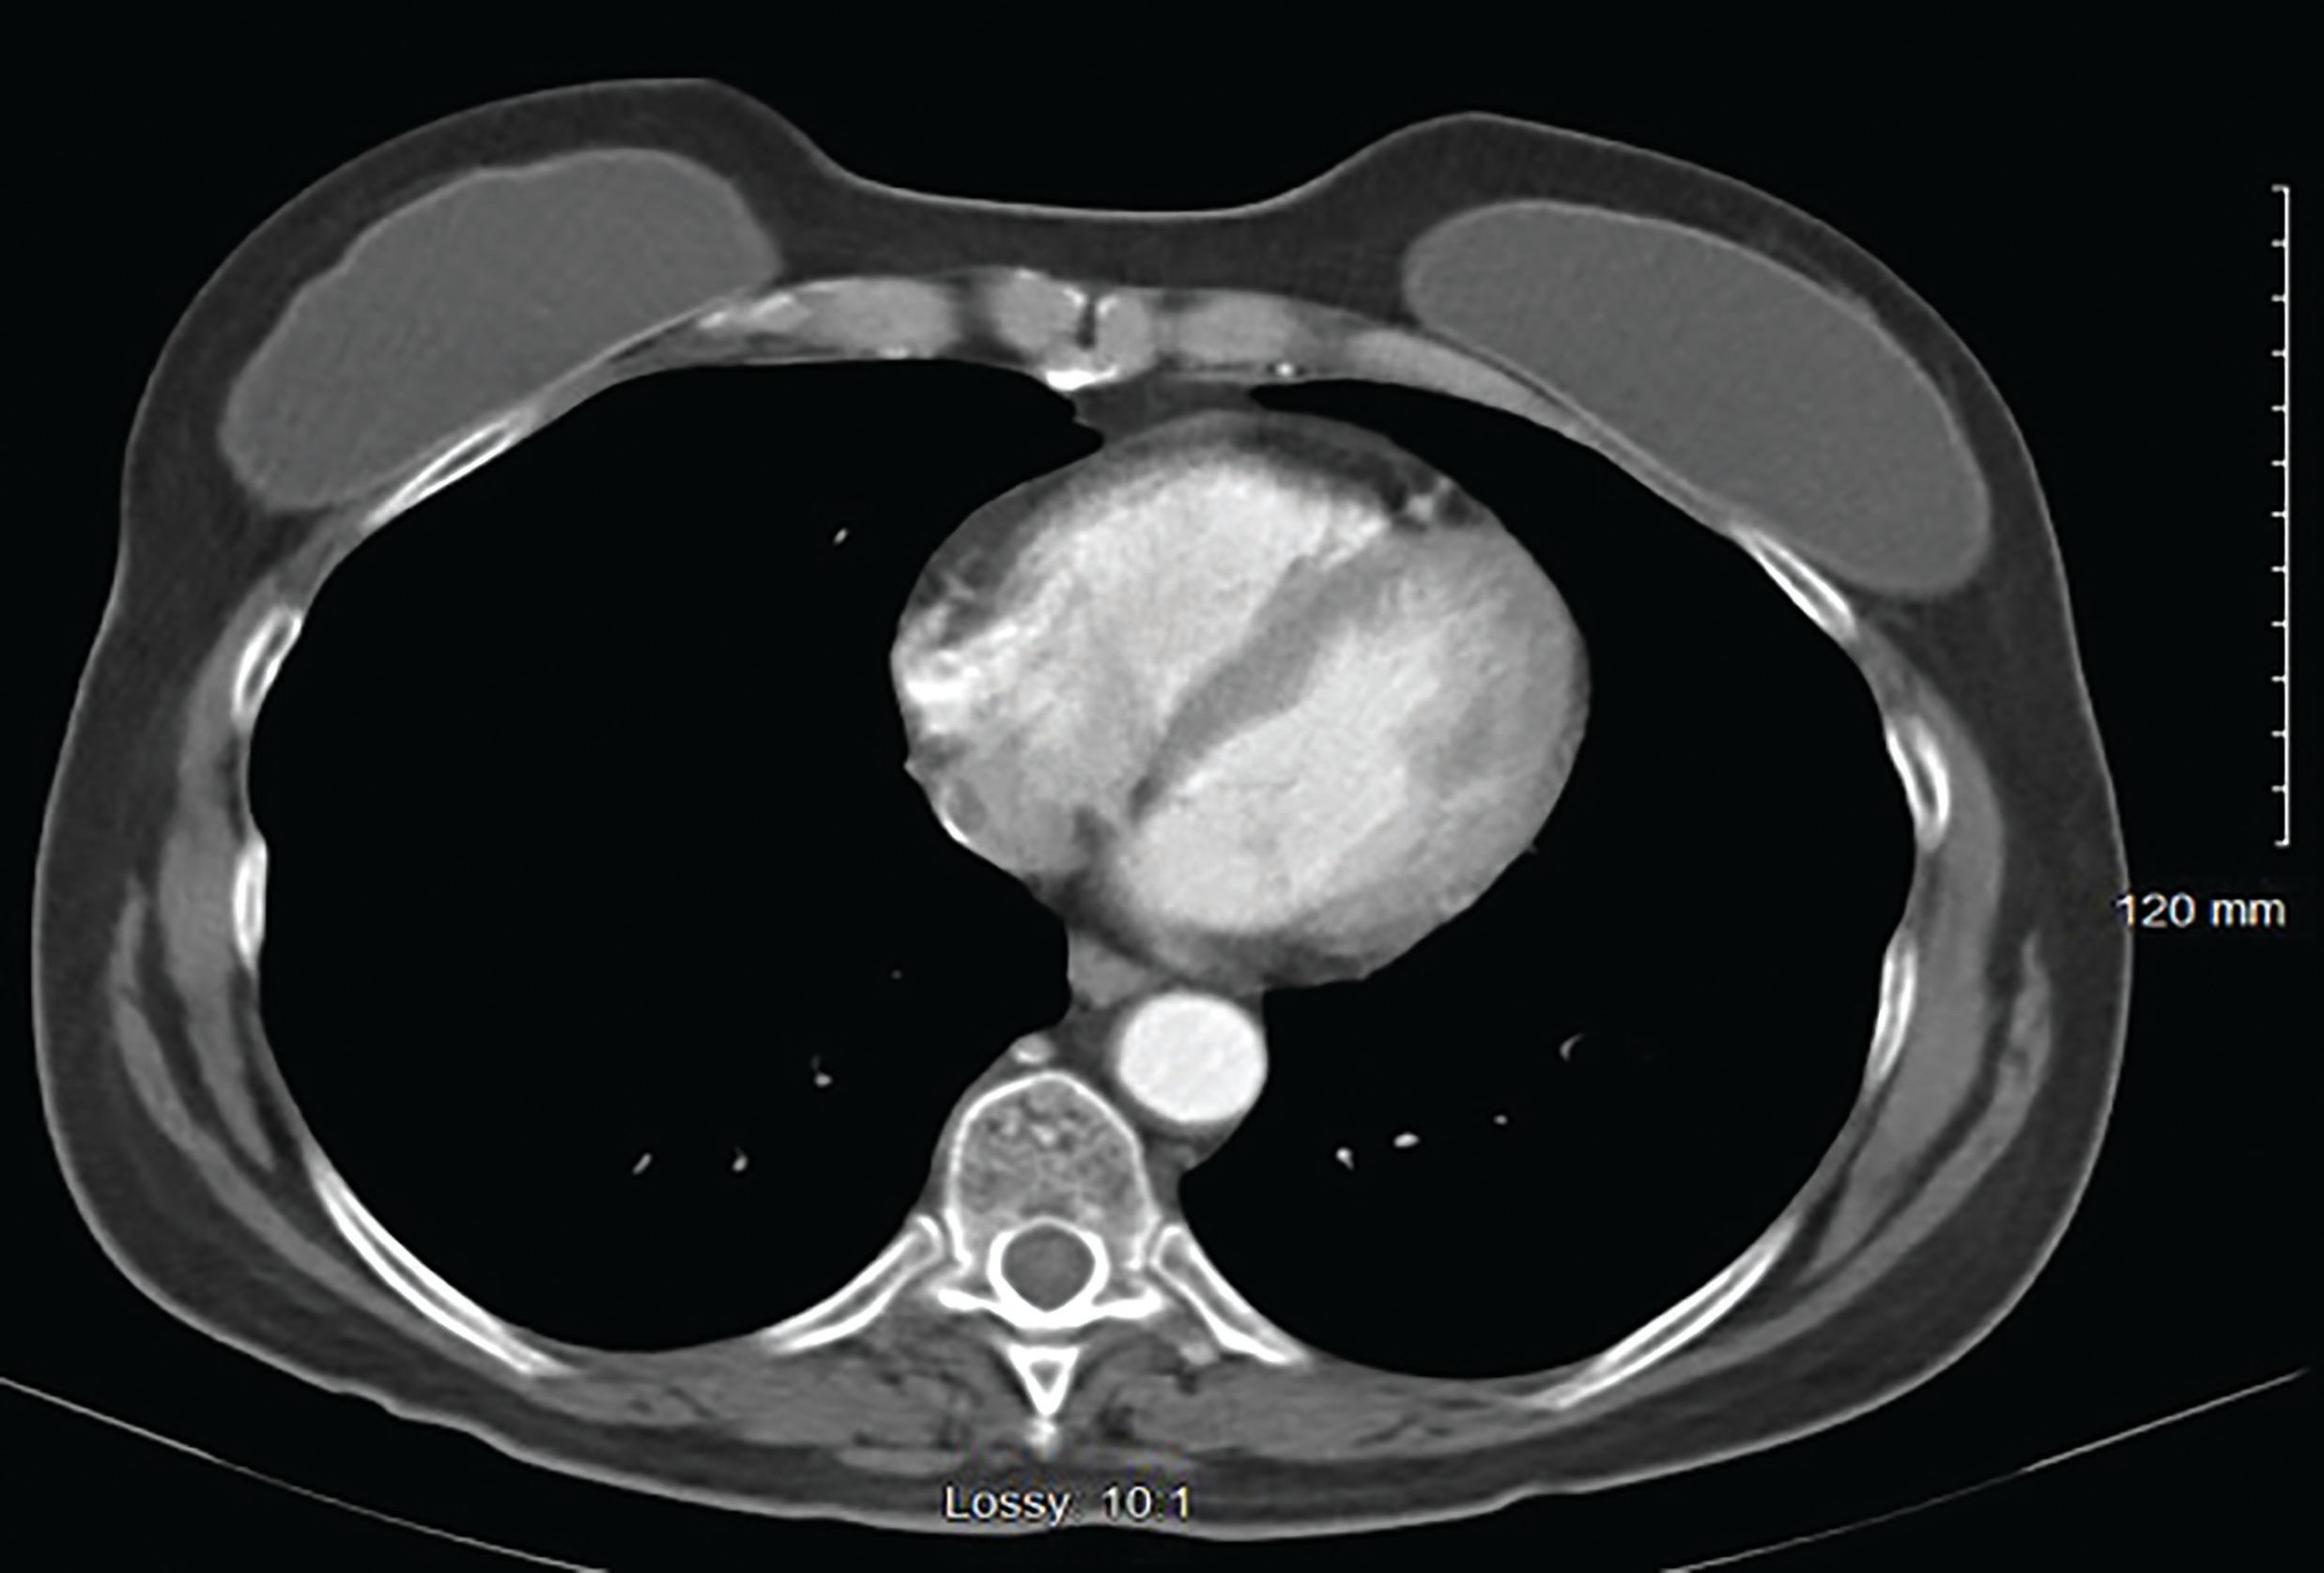

Figure 6. CT image of breast nodule after chemotherapy

Further work-up with CT scans of the abdomen and pelvis revealed adenopathy in the abdomen adjacent to aorta and left adrenal gland. She was started on second-line chemotherapy with paclitaxel 175 mg/m2 and carboplatin (area under the concentration time curve of 6) given intravenously every 3 weeks. After 4 cycles of chemotherapy, the breast nodule was no longer visible or palpable on physical exam (Figure 5). Restaging CT scans showed resolution of the breast nodule and axillary and abdominal lymphadenopathy (Figures 6).